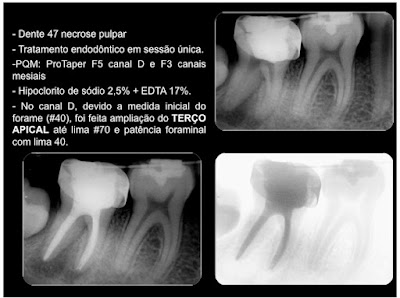

Tratamento endodôntico - dente 47 sessão única - forame amplo